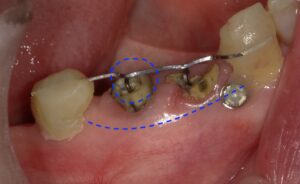

画像の丸点の部分ですが歯につけたフックと棒が

ぶつかりかなり挺出していることがわかります。

また青の横点線部分は歯茎ごと挺出しています。